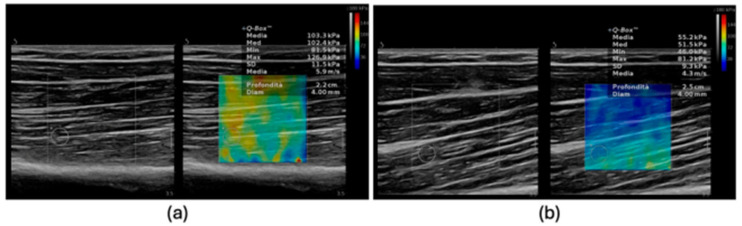

骨骼肌减少症是一种与年龄相关的骨骼肌质量、力量和功能的进行性丧失,是老年人残疾、生活质量下降和死亡率的主要原因。虽然目前的诊断方法,如双能x线吸收仪(DXA)、生物电阻抗分析(BIA)、磁共振成像(MRI)和计算机断层扫描(CT),被广泛用于评估肌肉质量,但它们在检测肌肉结构和成分的早期定性变化方面存在局限性。剪切波弹性成像(SWE)是一种基于超声的量化组织刚度的技术,已经成为一种有前途的工具,可以以无创、便携和可重复的方式评估肌肉的数量和质量。研究表明,SWE可以检测与肌肉减少症相关的肌肉力学特性的改变,为传统的形态计量学评估提供补充信息。初步证据表明,该方法具有良好的可重复性,在各种临床环境中具有可行性,并有可能纳入常规评估。这篇叙述性综述总结了目前在不同人群中使用SWE评估肌肉减少症的证据。

Sarcopenia, a progressive age-related loss of skeletal muscle mass, strength, and function, is a major contributor to disability, reduced quality of life, and mortality in older adults. While current diagnostic approaches, such as dual-energy X-ray absorptiometry (DXA), bioelectrical impedance analysis (BIA), magnetic resonance imaging (MRI), and computed tomography (CT), are widely used to assess muscle mass, they have limitations in detecting early qualitative changes in muscle architecture and composition. Shear Wave Elastography (SWE), an ultrasound-based technique that quantifies tissue stiffness, has emerged as a promising tool to evaluate both muscle quantity and quality in a non-invasive, portable, and reproducible manner. Studies suggest that SWE can detect alterations in muscle mechanical properties associated with sarcopenia, providing complementary information to traditional morphometric assessments. Preliminary evidence indicates its good reproducibility, feasibility in various clinical settings, and potential for integration into routine evaluations. This narrative review summarizes current evidence on the use of SWE for the assessment of sarcopenia across diverse populations.